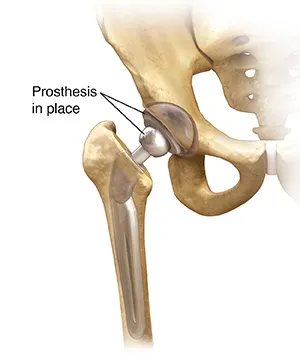

Total Hip Replacement

Total hip replacement surgery almost always reduces joint pain. During this surgery, your problem hip joint is replaced with an artificial joint, called a prosthesis.